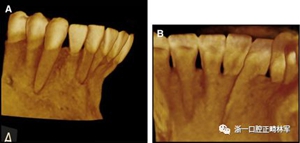

臨床檢查顯示固定保持器完好,弓絲沒有斷裂(圖13)。在下頜右側(cè)中切牙唇側(cè)和鄰近側(cè)切牙的舌側(cè)注意到有牙齦退縮。這些牙齒在退縮方向上存在顯著的扭矩差異。下頜的左側(cè)尖牙頰側(cè)錯(cuò)位,而右側(cè)尖牙舌側(cè)傾斜。三維射線照片證實(shí)了下頜右側(cè)尖牙面?zhèn)妊啦酃菃适?,右?cè)中切牙的喪失程度較輕。右側(cè)側(cè)切牙根也從舌側(cè)骨面上扭轉(zhuǎn)出來(圖14)。

圖14.三維立體圖像:A,面部和B,切牙根部的舌側(cè),剛?cè)〕龉潭ㄉ鄠?cè)保持器后。